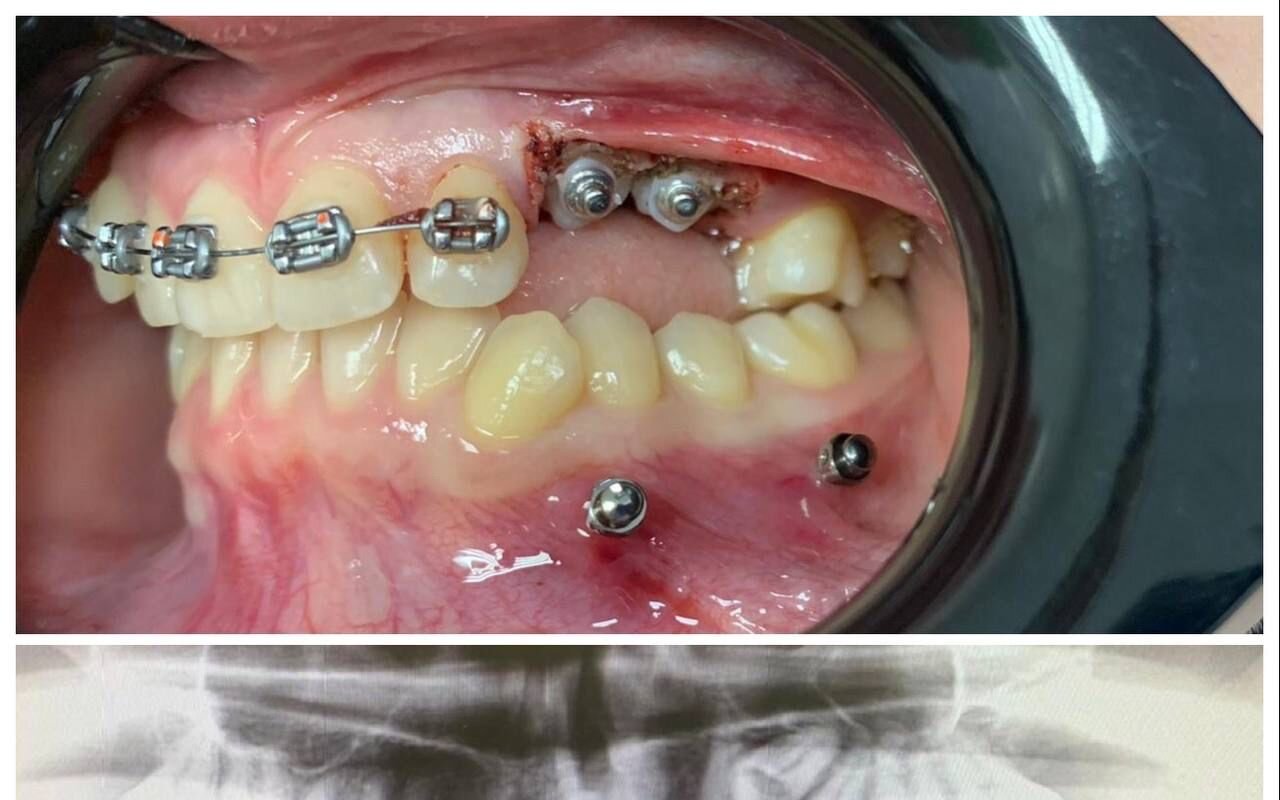

Стоматолог-ортопед, хирург, имплантолог

Синанян Хачатур Георгиевич является стоматологом-ортопедом, а также работает в сфере имплантологии и стоматологической хирургии. Хачатур Синанян в том числе делает пластику десны, уздечки губ и языка и тканей полости рта, устанавливает условно-съемные протезы, металлокерамические и безметалловые протезы, штифты, вкладки и виниры, а также выполняет несъемное и съемное протезирование зубов, микропротезирование зубов, шинирование зубов и синус-лифтинг.... Показать еще

Фото работ врача Хачатура Георгиевича Синаняна